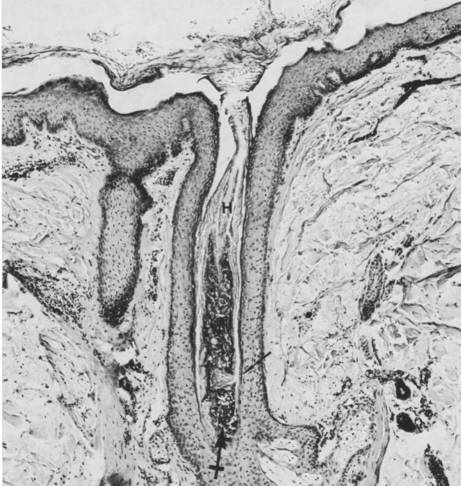

下图所示的是毛囊皮脂腺截面图。

(Follikel-Filamente,G.Plewig,1976)

毛囊皮脂腺累积于并局限于面部和上鼻,由巨大的卵泡管、纤细的毛发和巨大的皮脂腺组成。皮脂腺末端是由正常的鳞状上皮细胞排列组成的。